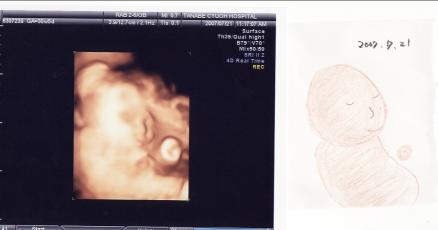

日時:2007年7月21日

場所:ママのおなかの中 (30週間と5日)

大きさ:BPD(頭の直径):8.02cm

FTA(腹部の断面積):50.69cm2

FL(大腿部の長さ)5.45cm

EFW(推定体重):1622g

やはり、最初はこちらを向いてくれず

DR.がねばってくれてようやく横顔をぱちり。

ほっぺぷっくりね。